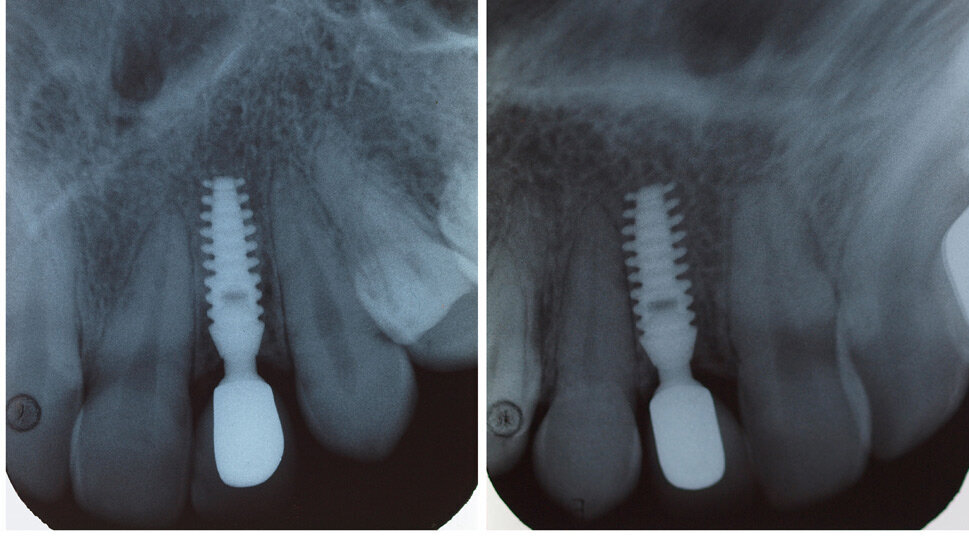

В маркетинга на денталните импланти често се набляга върху „простотата“, като ...